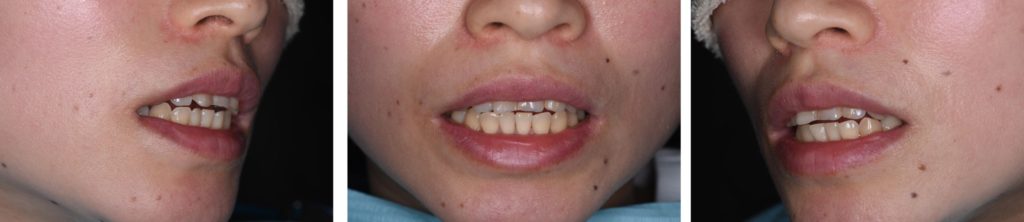

妊娠中の嘔吐習慣によるエロージョン(酸蝕症)と歯軸傾斜を短期間で改善した症例(インハウスアライナー、セラミック、デジタル)

Before

| 診断名 | 前歯部審美障害(酸蝕および咬耗による歯牙形態異常)および発音障害 |

| 年齢・性別 | 39歳 女性 |

| 治療方法 | デジタルセットアップ→診断→院内製作マウスピース型矯正装置による矯正治療→前歯部補綴 |